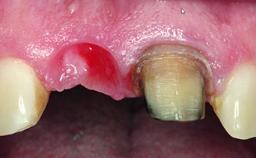

Replacement of a Compromised Upper Right Central Incisor: Hard- and Soft-tissue Augmentation, Late Placement of an RC Bone Level Implant

A 36-year-old male patient with a compromised maxillary central incisor was referred by his general dentist for consultation. The patient’s chief complaints were the gradual debonding of a temporary crown on the right central incisor and unsatisfactory esthetics due to an increasing diastema between the right central and lateral incisors. The patient reported a traumatic event some years previously, when a crown had been placed after root-canal treatment. The referring dentist wanted to provide a new crown restoration, but was concerned about the condition of the residual root. Anamnesis was negative for any other dental or periodontal pathology in the remaining dentition. The patient reported taking no medications: He was a smoker (10 to 15 cigs/day) and had realistic esthetic expectations.

Soft Tissue Contour and Volume Slightly compromised